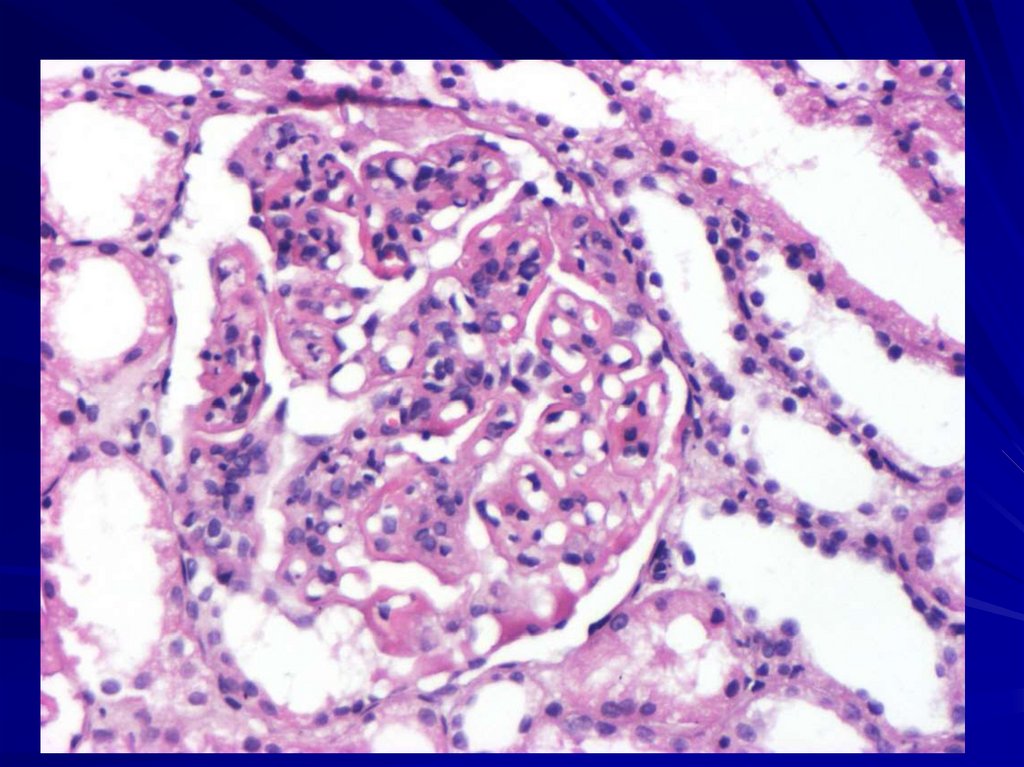

59. Микропрепарат № 102 Узелковый продуктивный миокардит (гранулематозный), (окр. г.+э., Б. ув.).

Локализация клеточных скоплений

– ревматических гранулем _______

(межмышечная соединительная

ткань, периваскулярно, в

адвентиции сосудов).

Клеточный состав «цветущей»

гранулемы ______________

(макрофаги, лимфоциты,

плазмоциты, фибробласты,

фиброциты).

Клеточный состав «рубцующейся»

гранулемы ___________

(макрофаги, плазмоциты,

фибробласты, аргирофильные

волокна, коллагеновые волокна).

В строме ________ (малокровие,

полнокровие, отек). Кардиомиоциты

____________ (атрофированы,

гипертрофированы, без

изменений).